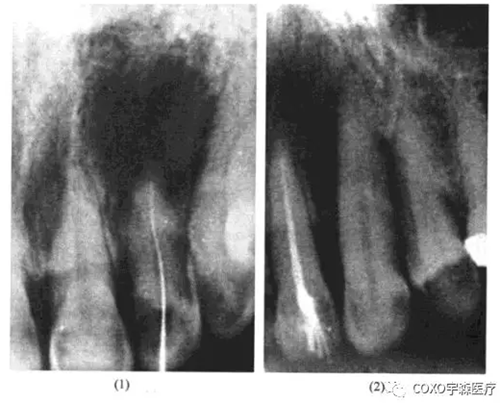

病例:

女性,54歲,左上唇炎癥腫脹一周在某中心醫(yī)院口腔科靜脈滴注抗生素未見好轉(zhuǎn)而來我科求治。檢查:[2唇側(cè)牙齦腫脹,有波動感,[2無齲,無牙體缺損,牙髓活力測試反應明顯,X線片示:[2根尖區(qū)有1cm×1.5cm之透射陰影,邊緣整齊。當日處理:[2唇側(cè)切開引流待急性炎癥消退后,在局麻下行活髓摘除術,牙髓完整,3日后完成根管充填,并行囊腫摘除術。術中見[2唇側(cè)骨板有極小的穿破,按常規(guī)刮除炎性肉芽組織,肉芽多在[2之腭側(cè),送病理切片;手術診斷為2根尖周囊腫,病理診斷亦為[2根尖周囊腫;3個月后復查,2無癥狀,X線片示:原根尖周病變已痊愈(圖13-4)

分析與評述

由于[2為活髓牙,根尖周囊腫的診斷不能成立。由于X線片示囊腫位于[2之根尖而非[23之間,術中亦證實囊腫在[2之根尖偏腭側(cè),故球上頜囊腫之診斷亦可排除,最后診斷應為切牙管囊腫。